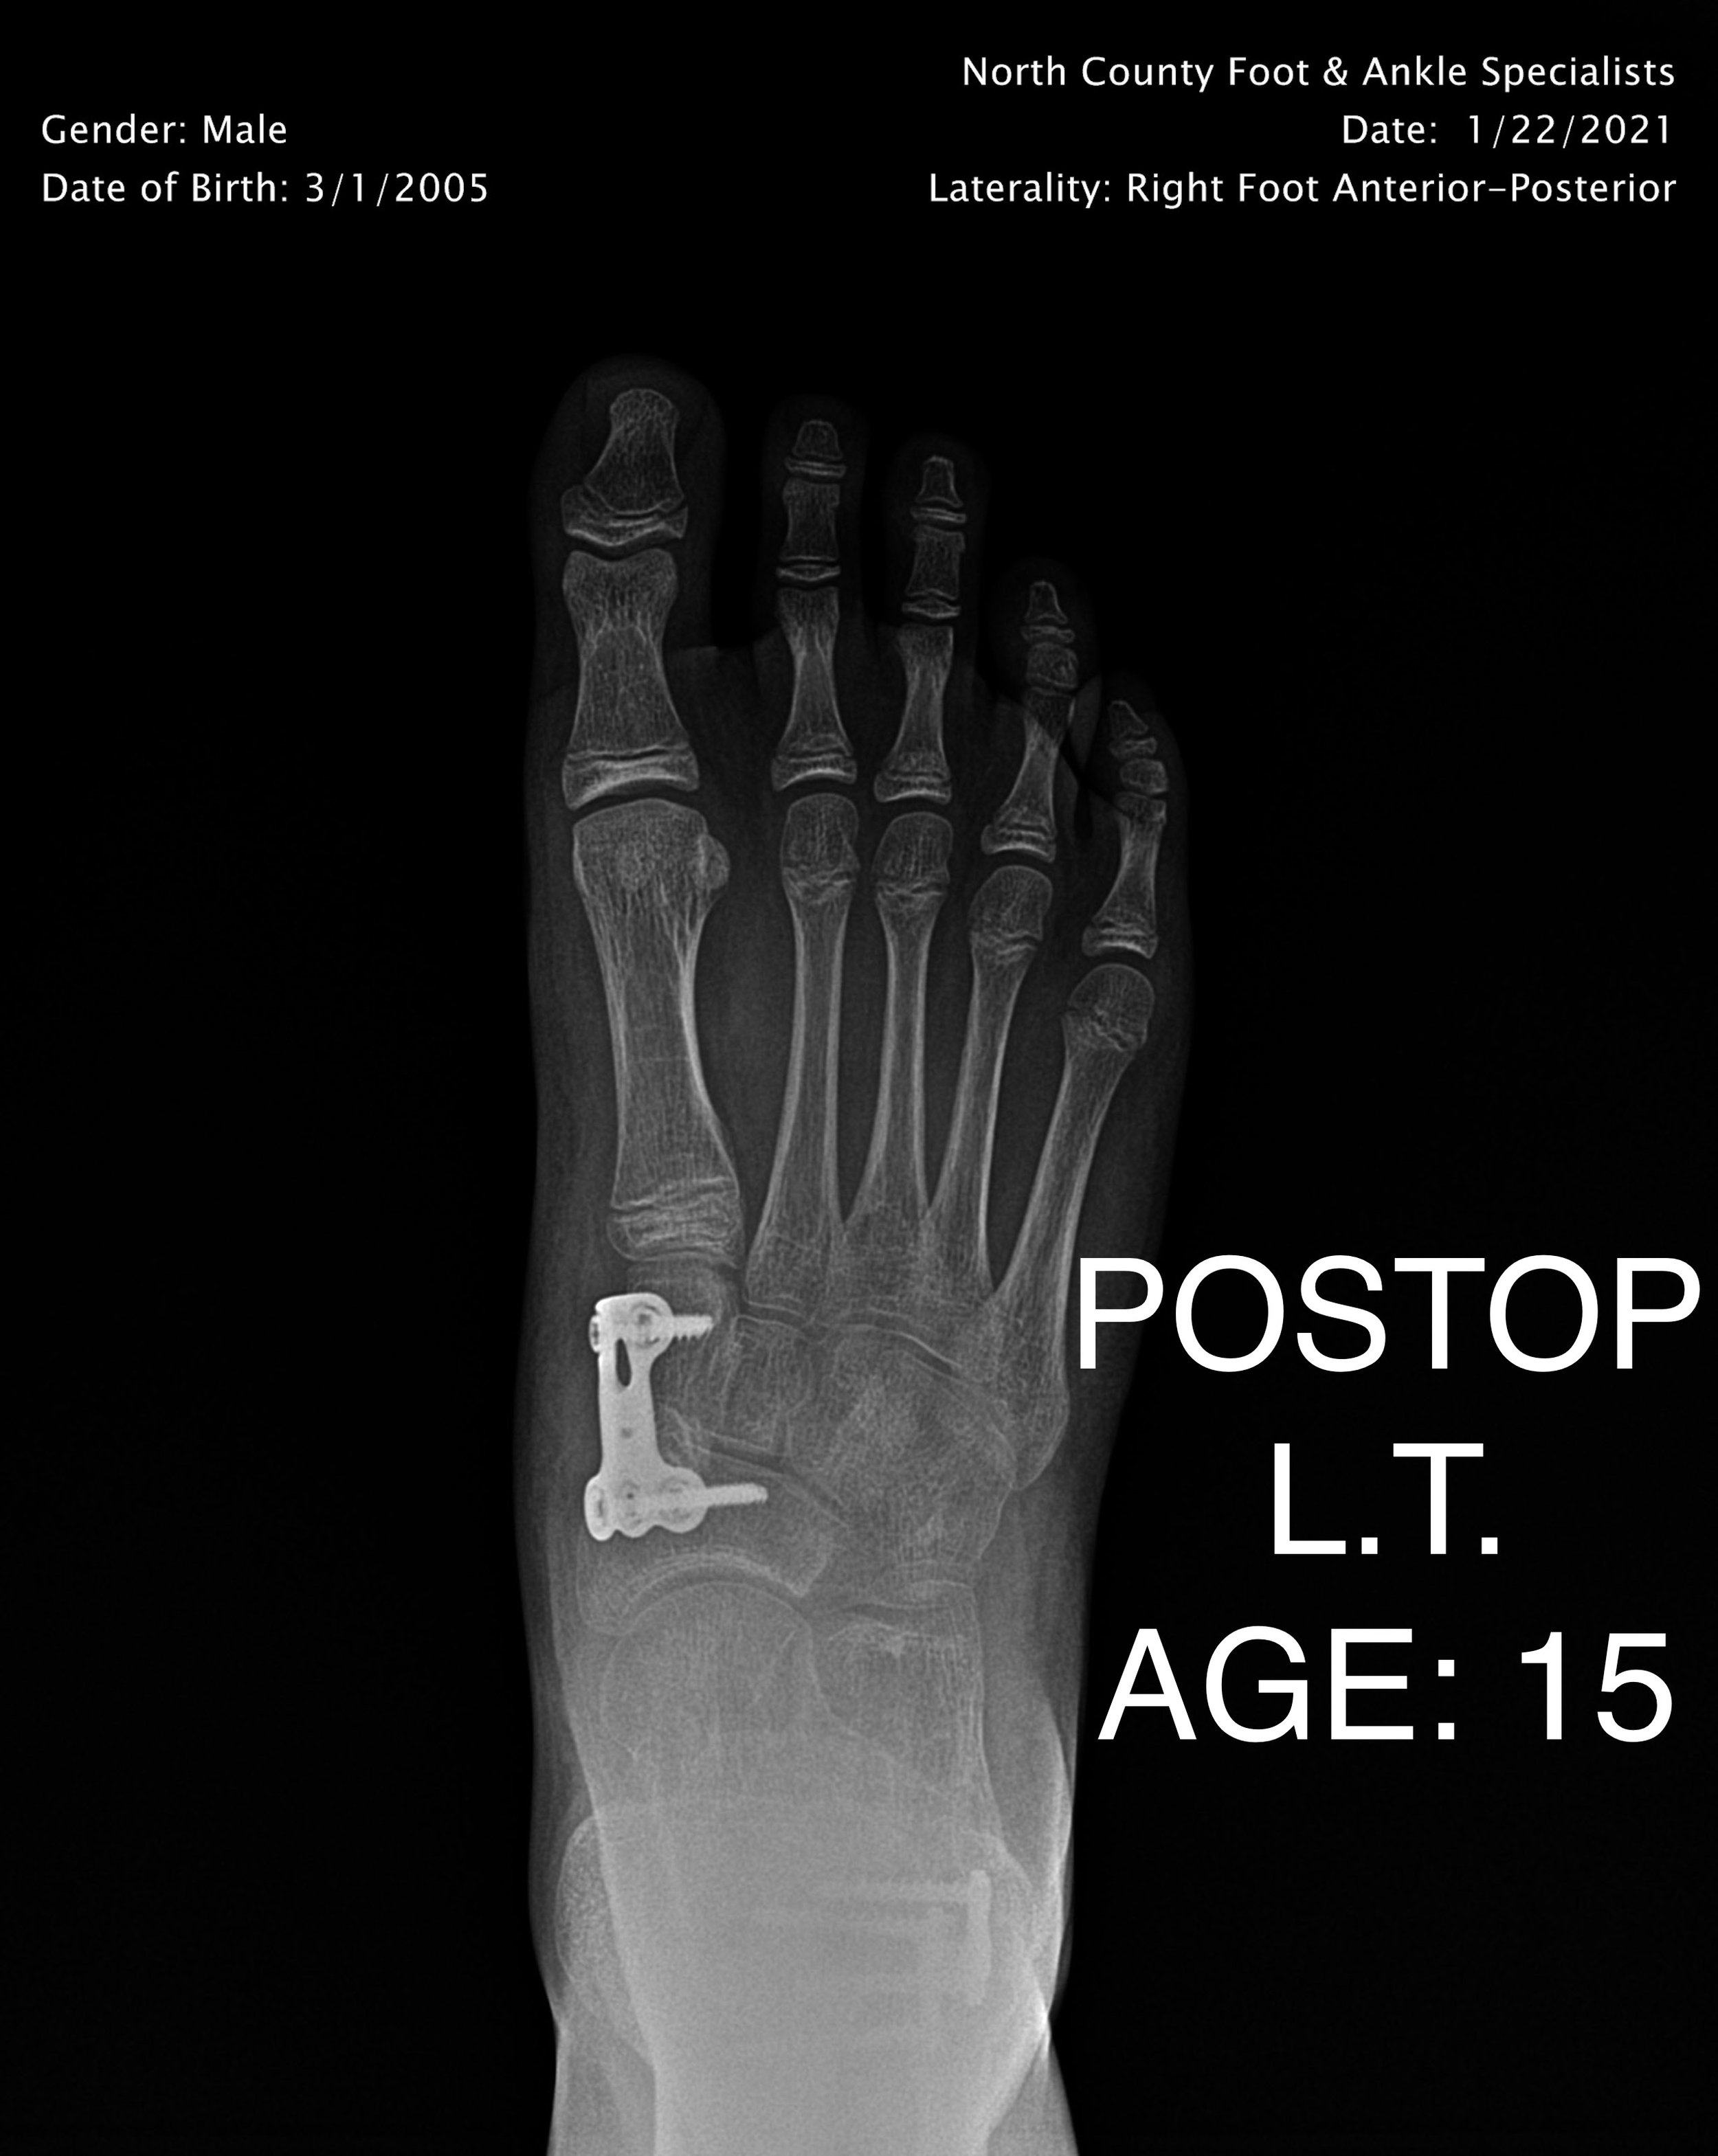

PEDIATRIC FLAT FOOT